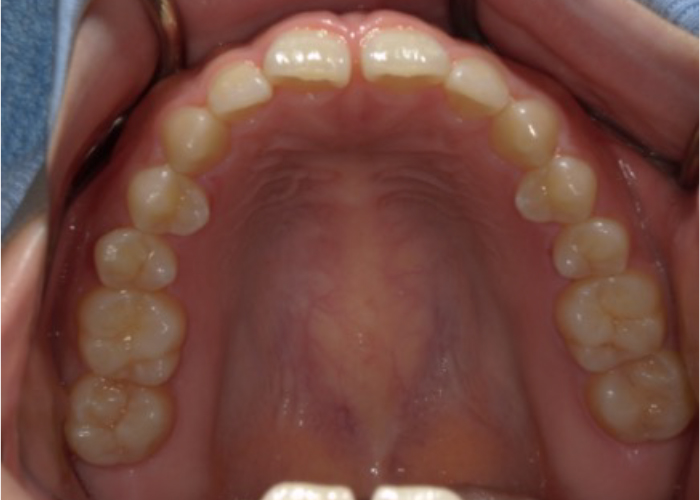

全体的ながたつきを改善したい